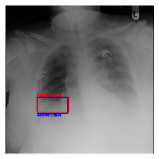

CXR8 [21] is one of the most commonly accessible radio-logical examination for many lung diseases. The data consists of 112,120 images collected by 30,805 patients. As shown in Table I, nine class labels of normal state and eight diseases including cancer are defined for classification. The data is divided into training set and test set, and the classification accuracy and ROC curve with several well-known deep network such as VGG16, GoogLeNet, and ResNet, are reported on the original paper [21]. In addition, 984 Bounding Boxes (B-Box) are provided for localization. Fig. 5 shows image examples of CXR8. The red rectangle in the image shows given B-Box.

IV-D Investigation of the generated heatmap

By using the training result of the Adaptive DBN, the heatmap images were generated in addition to detection of B-Box. The heatmaps in Fig. 10 to Fig. 14 show the detection result of B-Box and the generated heatmap for some images. The red and blue rectangles in the image are given B-Box and detected B-Box, respectively. A heatmap is represented by the continuous value of range , where the color map is jet color array (red means high value, while blue means small value). The diseases for detected B-Boxes in Fig. 10 to Fig. 14 were as follows; Infiltration (Fig. 10), Mass (Fig. 10), Nodule (Fig. 10), Mass and Pneumothorax (Fig. 10), Atelectasis (Fig. 14), Infiltration (Fig. 14), Atelectasis (Fig. 14), Atelectasis (Fig. 14).

Overall, the red area of the generated heatmap included in both the given B-Box and detected B-Box. On the other hand, the blue or yellow areas didn’t include in these B-Boxes. This tendency was seen in not only large diseases (e.g. Cardiomegaly or Infiltration) such as Fig. 10, but also small diseases (e.g. Mass or Nodule) such as Fig. 10. We consider that the experimental results caused by the discrete heatmap with binary output of final RBM layer instead of continuous heatmap. As a result, the red regions represents localization with strong relation to diseases and blue regions represents localization with weak relation. The generated heatmap shows the portion with strong relation more clearly.

In Fig. 14, the detected B-Box was located at a little upper than the given B-Box. The red area of the heatmap was also at upper position. The detected B-Box is slightly larger than the given B-Box. The detected B-Boxes are almost same as the given B-Boxes except the different size. For better detection capability, the feature of the generated heatmap will be investigated with the medical specialists.